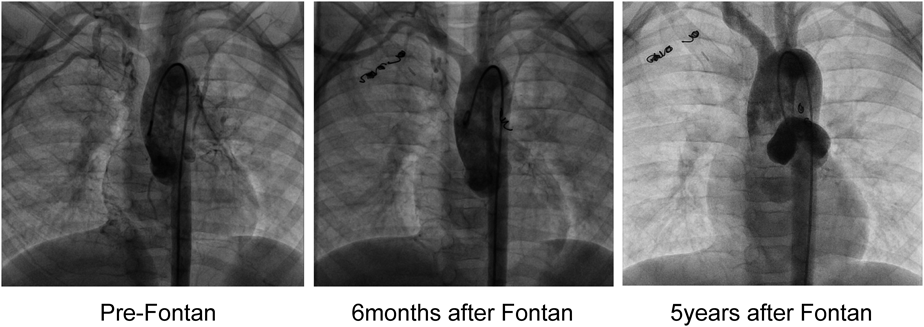

当院では主に内胸動脈からのAPCAで肺静脈まで造影されるものを対象にコイル塞栓を行っているが,Fig. 1に示す症例のように術前にAPCAが残存していても,Fontan循環を確立することで術後APCA flowが減少する症例を多く経験する.術前のコイル塞栓の目標を考えるとき,APCA flowの推移を考慮することは重要と思われるが,この点について論じた報告は少ない.

Fig. 1 Transition of APCA in a patient with Tricuspid Atresia

APCA=aorto-pulmonary arterial collateral arteries